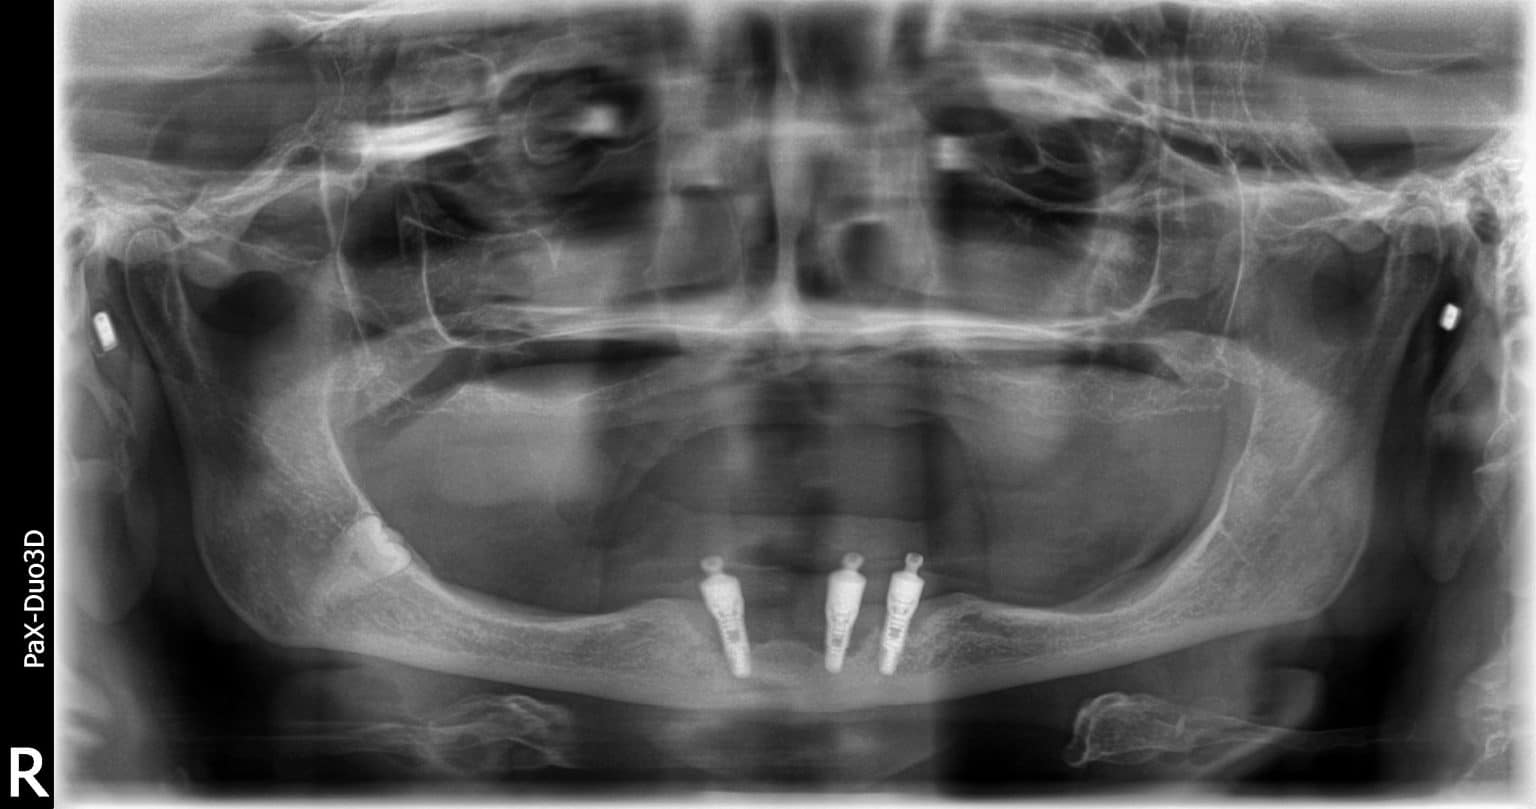

Dental Implant Problem . There are methods to fix these reasons for failure, but it can be a long and invasive process. Here, learn six things that impact the success of dental implants. What can i do about them myself, and what requires a professional? If your dental implant fails, you and your dentist can decide if you should replace the implant or try another option. Dental implant surgery is a procedure that replaces tooth roots with metal, screwlike posts and replaces damaged or missing teeth with artificial teeth that look and. Dental implants are permanent false teeth. Dental implants have a high success rate, but some people experience dental implant failure. Medically reviewed by zilpah sheikh, md on february 01, 2024. Dental implants are a groundbreaking modern solution to a problem that's historically worried humans: Reasons for dental implant failure include teeth grinding, an allergic reaction to the materials used, poorly made dental impressions, infection, nerve damage, movement of the implant, issues with underlying jawbones, and various medication conditions. What problems are common with dental implants? A dentist may recommend dental implants for you if you’re missing teeth or need.

Dental implants have a high success rate, but some people experience dental implant failure. There are methods to fix these reasons for failure, but it can be a long and invasive process. Dental implants are permanent false teeth. A dentist may recommend dental implants for you if you’re missing teeth or need. What can i do about them myself, and what requires a professional? If your dental implant fails, you and your dentist can decide if you should replace the implant or try another option. Medically reviewed by zilpah sheikh, md on february 01, 2024. Dental implants are a groundbreaking modern solution to a problem that's historically worried humans: Reasons for dental implant failure include teeth grinding, an allergic reaction to the materials used, poorly made dental impressions, infection, nerve damage, movement of the implant, issues with underlying jawbones, and various medication conditions. What problems are common with dental implants?